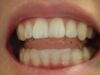

Es erfolgen die Maßnahmen der funktionellen Erstuntersuchung und die Herstellung und Eingliederung eines adjustierten Aufbissbehelfs zum Nachweis einer CMD.

Es erfolgen die Maßnahmen der klinisch manuellen Erstuntersuchung und nachfolgend die Maßnahmen zu Herstellung und Eingliederung eines adjustierten Aufbissbehelfs